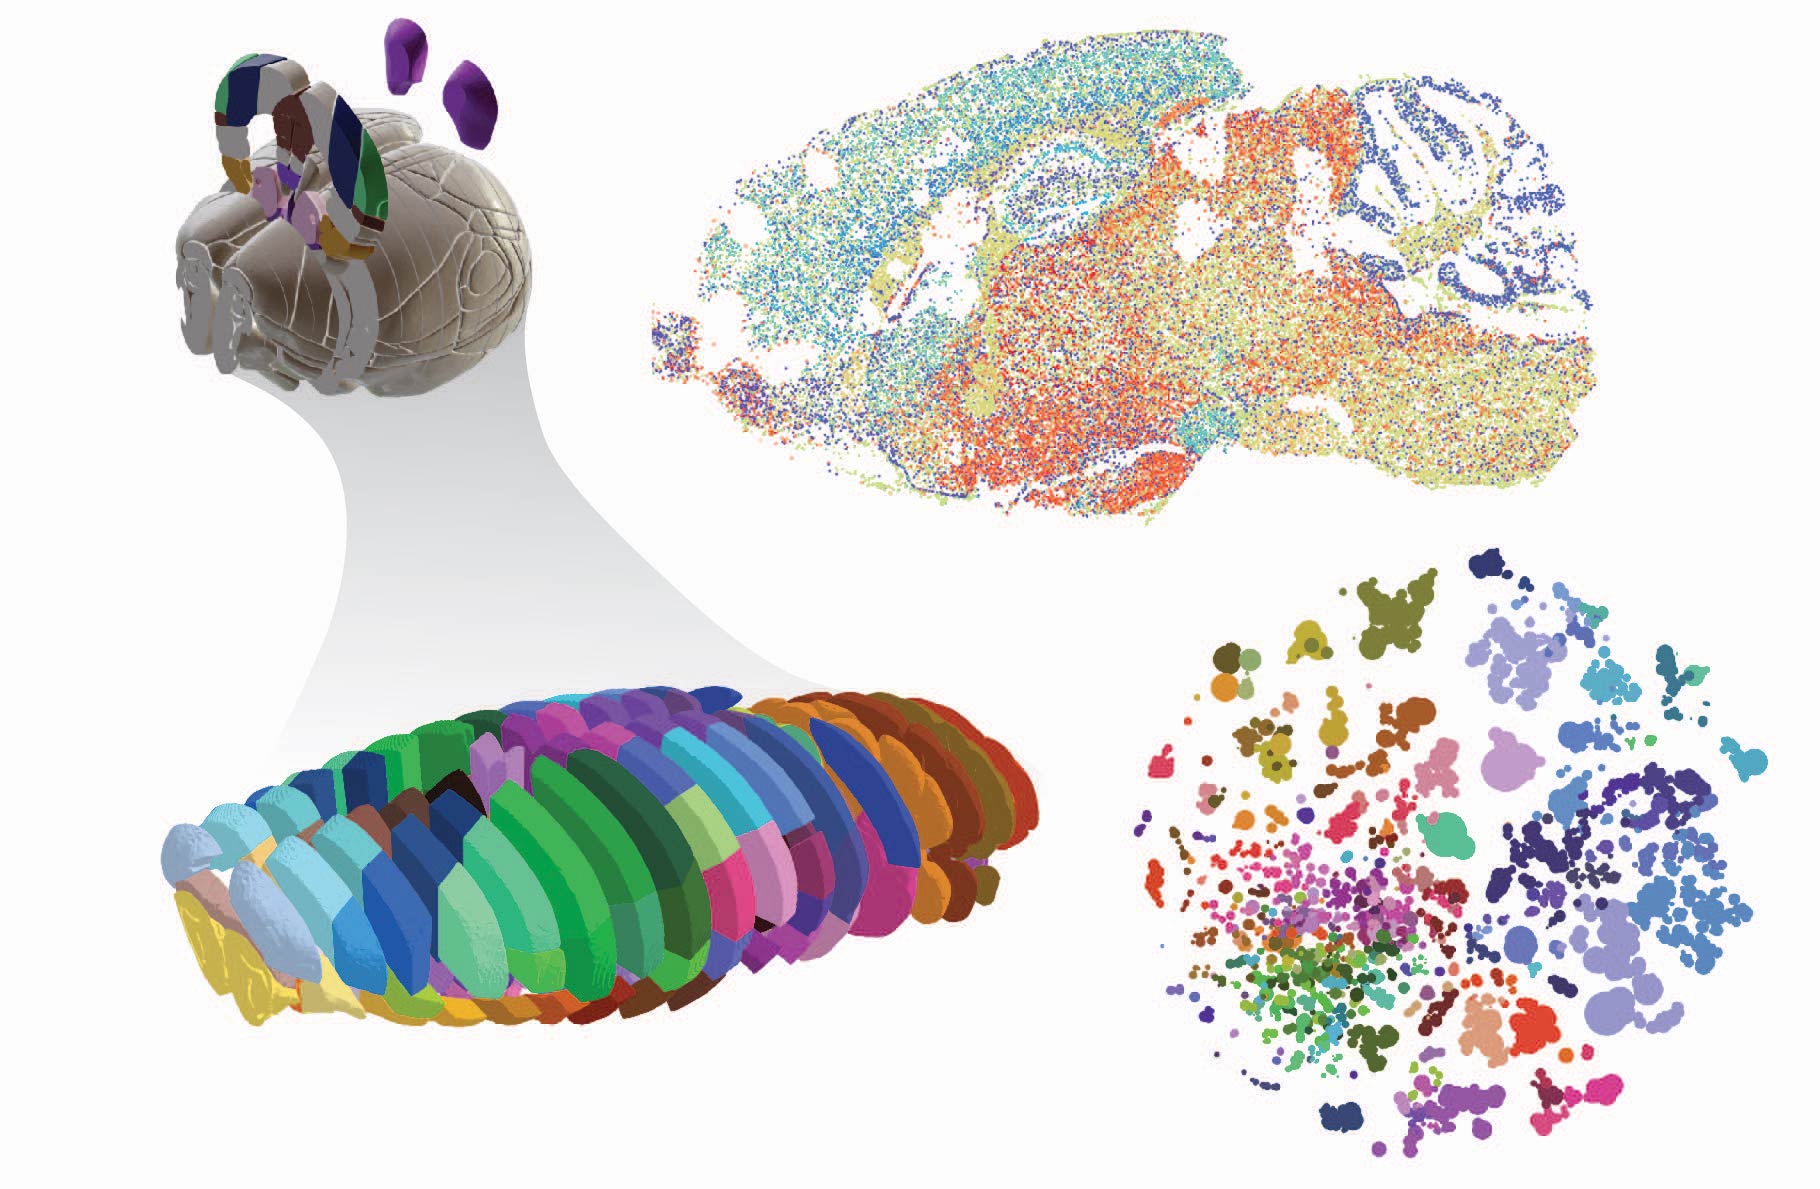

Коннектом мозга: визуализация связей и нейронных путей

Раздел: Мудрость в фокусе